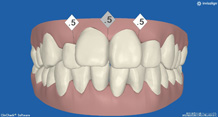

正面から観たところです。

全て乳歯です。反対咬合です。まだ幼児なので、お子様にかかる負担などをよく考えた上で、治療します。

反対咬合です。